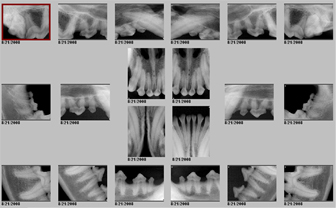

Dental radiographs allow us to examine root and bone health. Problems below the gum line can exist even when the surface of the mouth, gums and teeth appear normal. These xrays can provide evidence of abcesses, root resorbtion and even bone loss. 60% of periodontal disease found in dogs and cats is below the gum line.